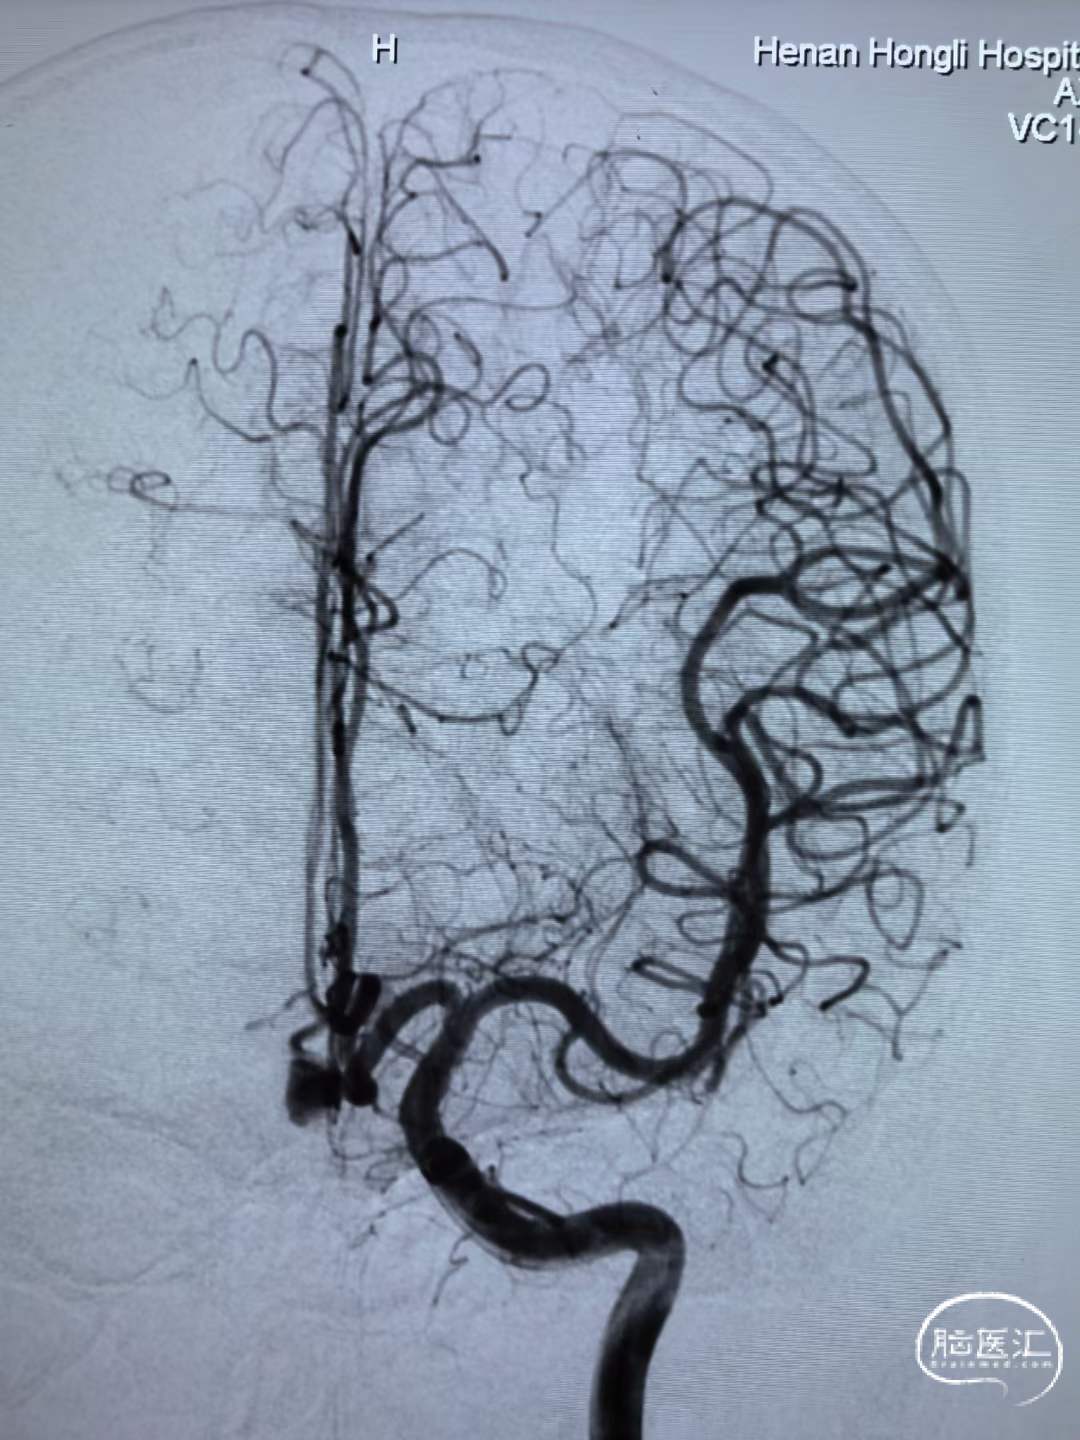

男性,52岁,前交通动脉瘤破裂来院就诊。

造影见前交通破裂动脉瘤,动脉瘤大小约7mm*12mm。